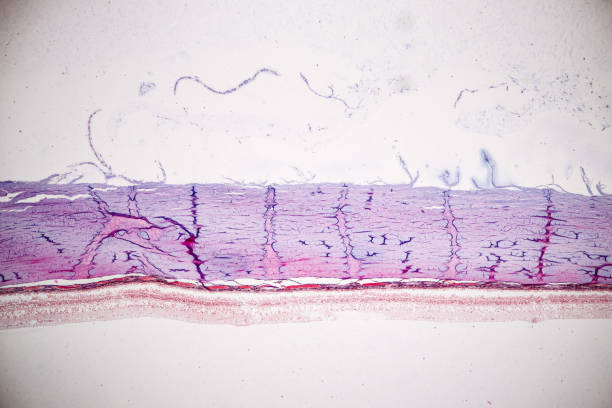

대표적으로 녹내장의 원인은 안압상승으로 인해 시신경이 손상원인이 녹내장 질환을 발생하게 합니다. 나이가 들면 노화가 진행됨으로써 눈의 각 부분 조절능력이 떨어져 안구 내의 안압이 높아지면서 이로 인해 뇌로 연결되는 시신경이 손상되면서 녹내장이 발생됩니다. 녹내장이 나타나면 시야가 좁아지면서 심하면 실명할수도 있습니다. 녹내장을 유발하는 대표적인 원인에 대해 알아보겠습니다.

녹내장 원인 두 번째는 고도 근시입니다. 고도 근시는 안구의 길이가 상대적으로 길어진다고 알려져 있습니다. 안구의 길이가 길어질수록 안구와 연결되는 시신경을 지지하는 구조가 얇아지고 힘을 덜 받게 되는데 이로 인하여 구조가 약해지면서 안압이 점차 시신경으로 전달되어 녹내장을 유발할 수 있습니다.